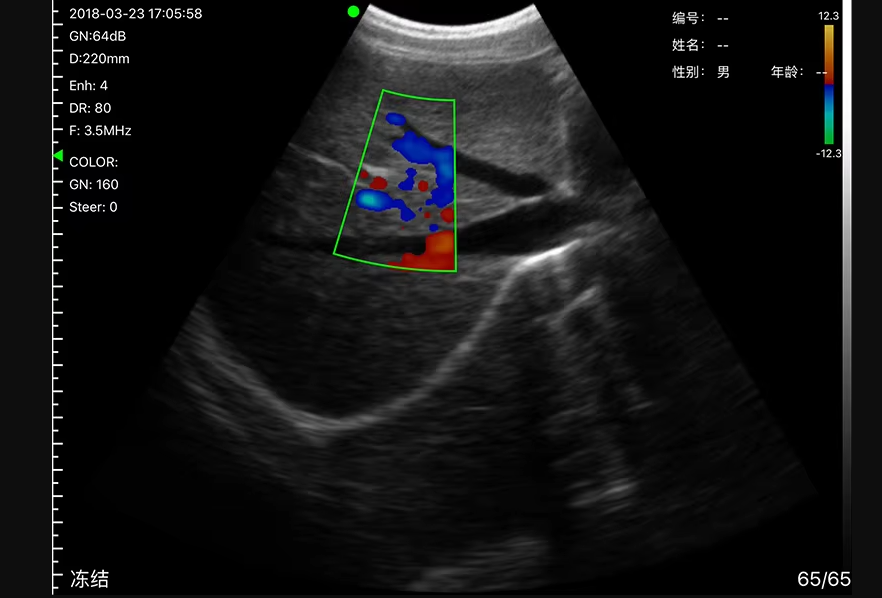

High-Quality Imaging

With advanced digital imaging technology, this wireless ultrasound probe price in Bangladesh offers excellent image clarity, deep penetration, and low noise. It helps doctors make quick and accurate diagnoses, improving patient care.

Abdominal Examination

Emergency Diagnosis